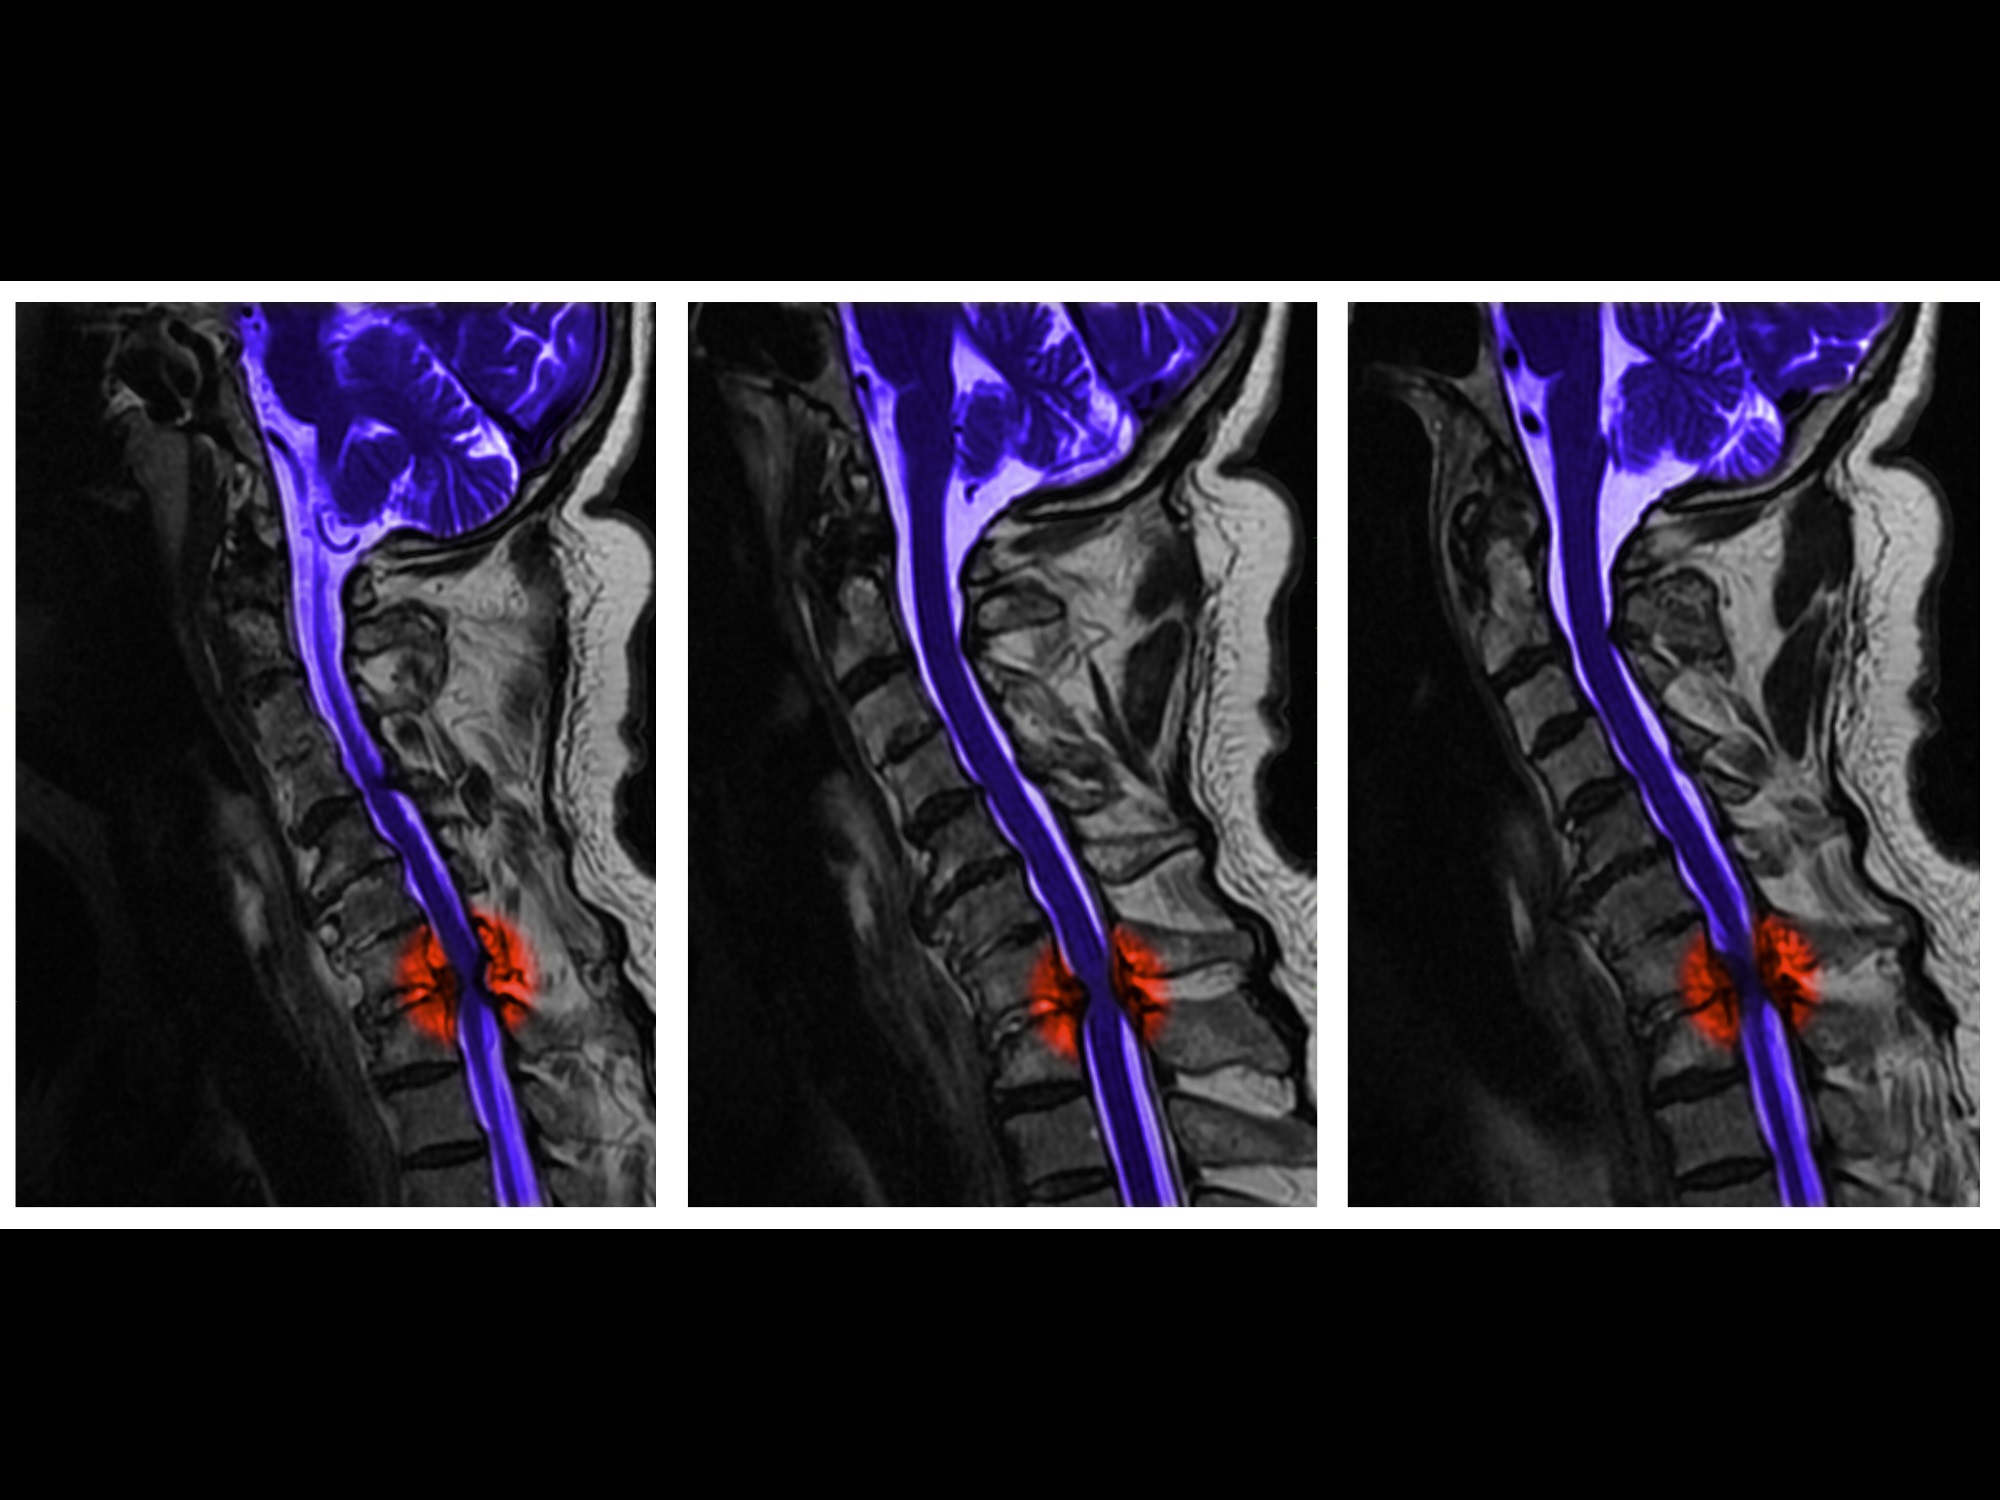

截瘫是瘫痪的一种,顾名思义就是因为脊髓受损平面以下的身体及四肢的感觉、运动和发射的消失。打个比方就是电线断了,开关和电器都*工罢**。常见的截瘫病因有以下几种:脊柱压缩性骨折、脊髓损伤、横断性脊髓炎、肿瘤、结核和脊髓空洞症等等。